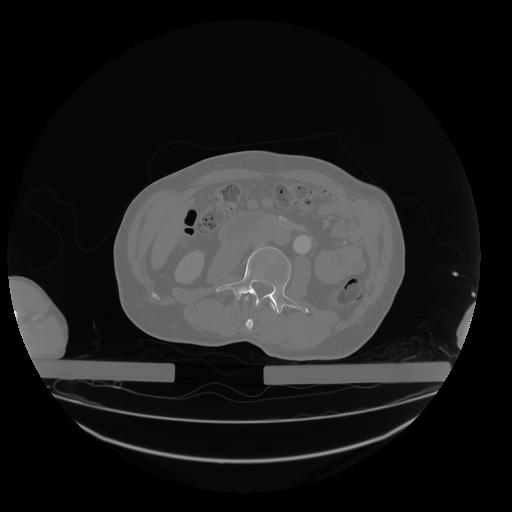

28 CUERPO,CE,Vol,2.0,CUERPO,,